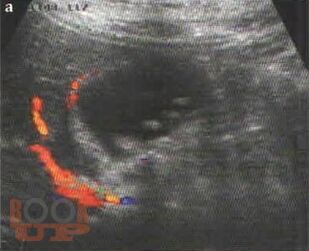

В учебном пособии представлена диагностика острого холецистита по данным ультразвукового исследования. Особое внимание уделено оценке положительных и отрицательных эхографических признаков острого холецистита на фоне проводимой терапии.